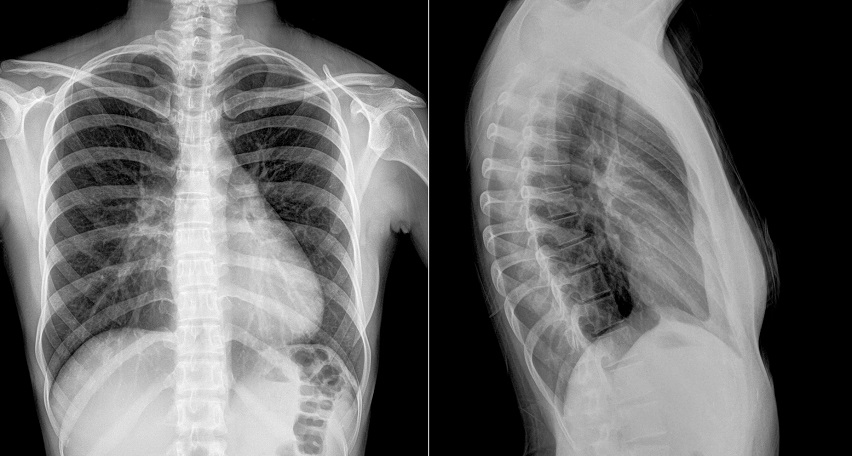

Рентген грудины предоставляет важную информацию о состоянии органов, тканей и полостей. На снимках видно:

- Легкие. Можно оценить объем, структуру, выявить изменения, такие как заполнение воздухом, жидкостью или опухолевидные образования.

- Сердце, грудной отдел аорты, легочные артерии. Заметно увеличение сердца, жидкость в перикарде, повреждение аорты.

- Кости с трещинами, новообразованиями или костными отломками.

- Органы средостения. Пищевод, трахея, лимфатические узлы.